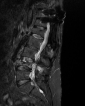

Eski Lomber Stabilizasyon Sistemi Altında Kırık (2)

Ağustos 2023